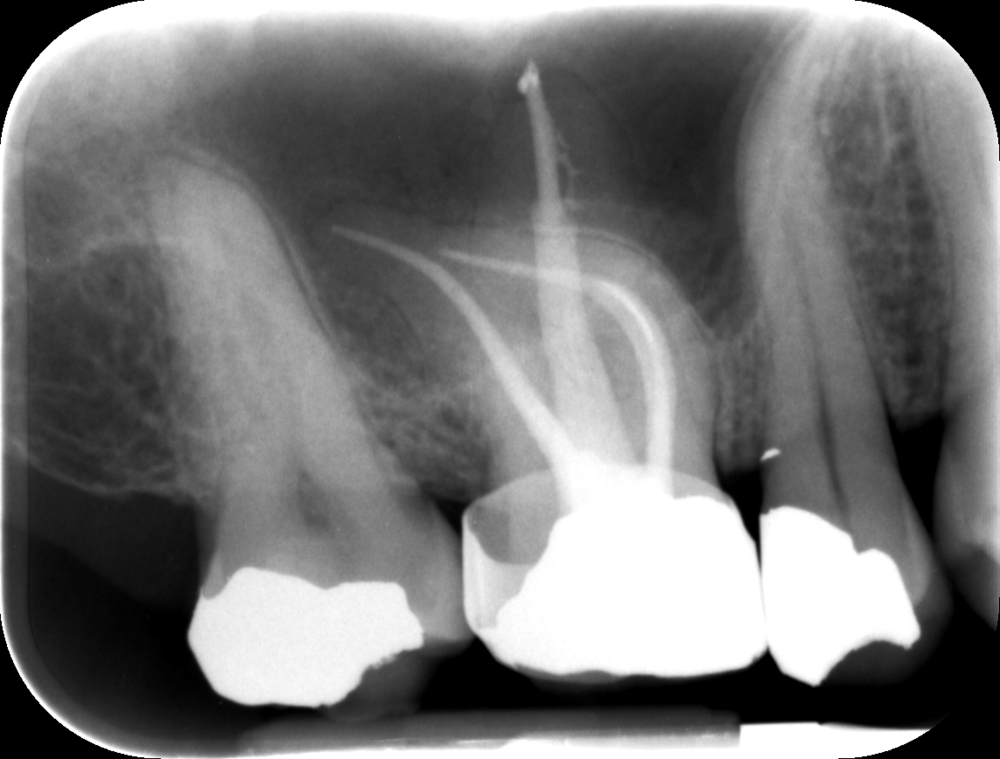

An X-ray is taken initially to fully understand the shape of the root canal and to check for infection in and around the affected area of the tooth.

root canal treatment steps